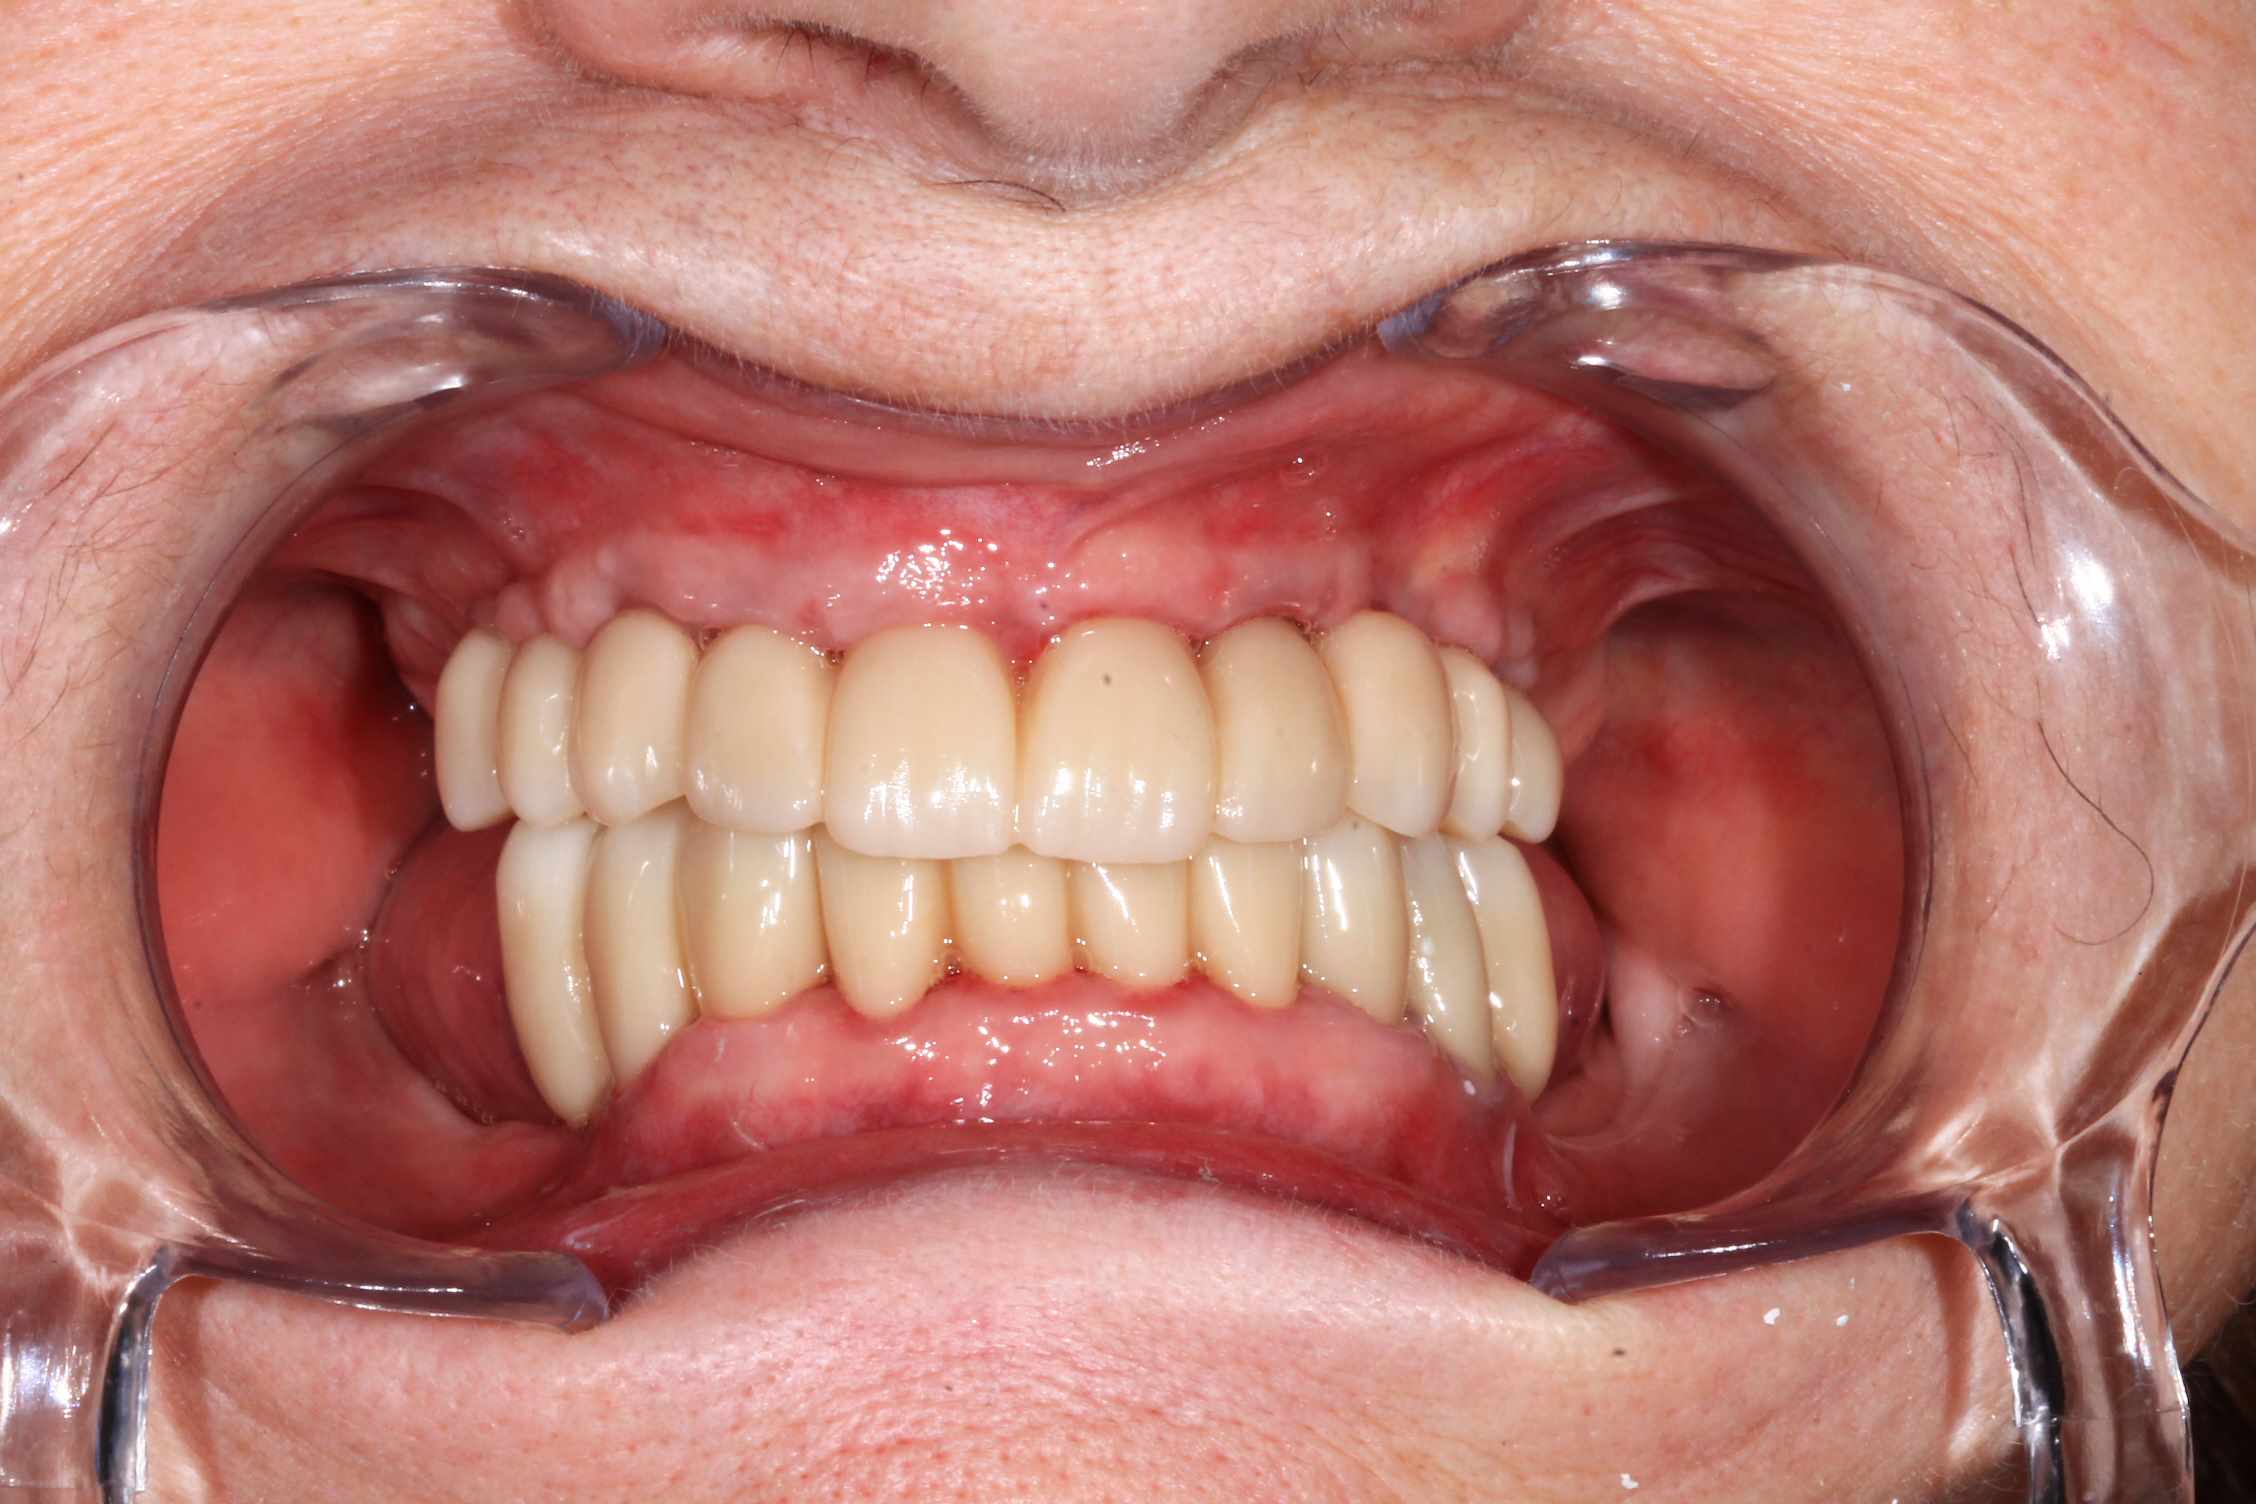

Cas 5 : extraction et all on 4. en bas , pas du tout d'os : décision de bridge complet avec une extension de chaque coté.

Modélisation : labo lio. Design et impression du guide : Teeth projet. Bridge full zircone katana myio rosenscrew en mise en charge instantanée , labo LIO.

Fixation du guide de forage sur le guide clavette. pose des implants, des piliers ( tres classique ), et du bridge zircone rosenscrew. Stickybone The Graft, sutures suspendues et résultat post op et un mois.